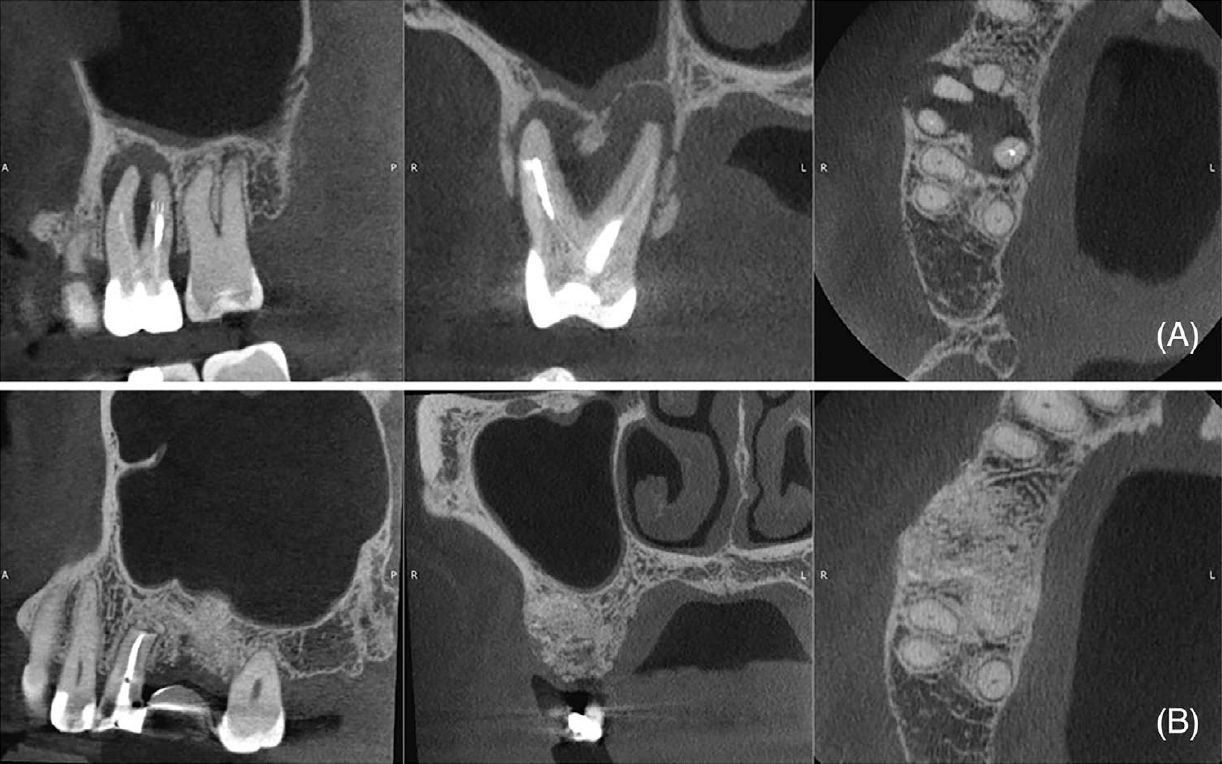

Фото 8. (A) Исходное КТ (сагиттальная, корональная и аксиальная проекции), демонстрирующее очаг пониженной плотности в области зубов 18 и 17, утолщение слизистой оболочки верхнечелюстной пазухи, кортикальную фенестрацию и ороантральное сообщение (стрелки). (B) КТ через 6 месяцев после операции (сагиттальная, корональная и аксиальная проекции), демонстрирующее образование кости, нормализацию состояния слизистой оболочки пазухи, восстановление кортикальной пластинки и закрытие ороантрального сообщения